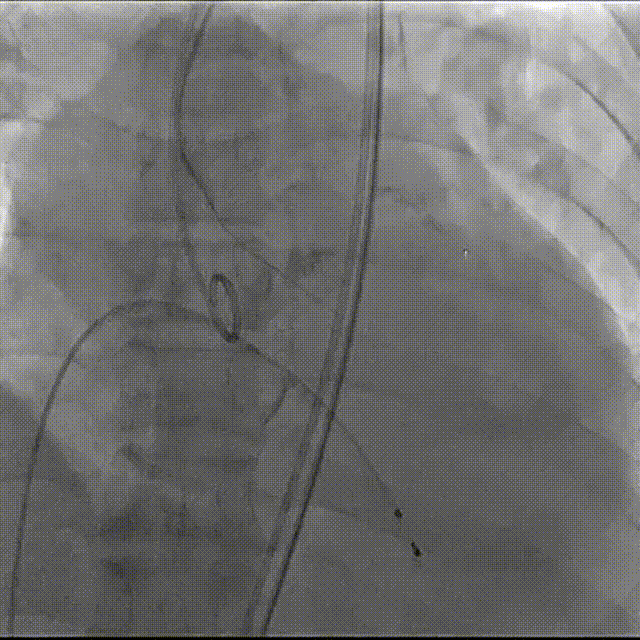

导丝跨瓣

23mm球囊预扩

球扩后上输送器之前,心脏停跳,心脏按压复律。

第一次瓣膜定位,心脏再次停跳,按压复律

第二次完全释放

球囊后扩

最终造影